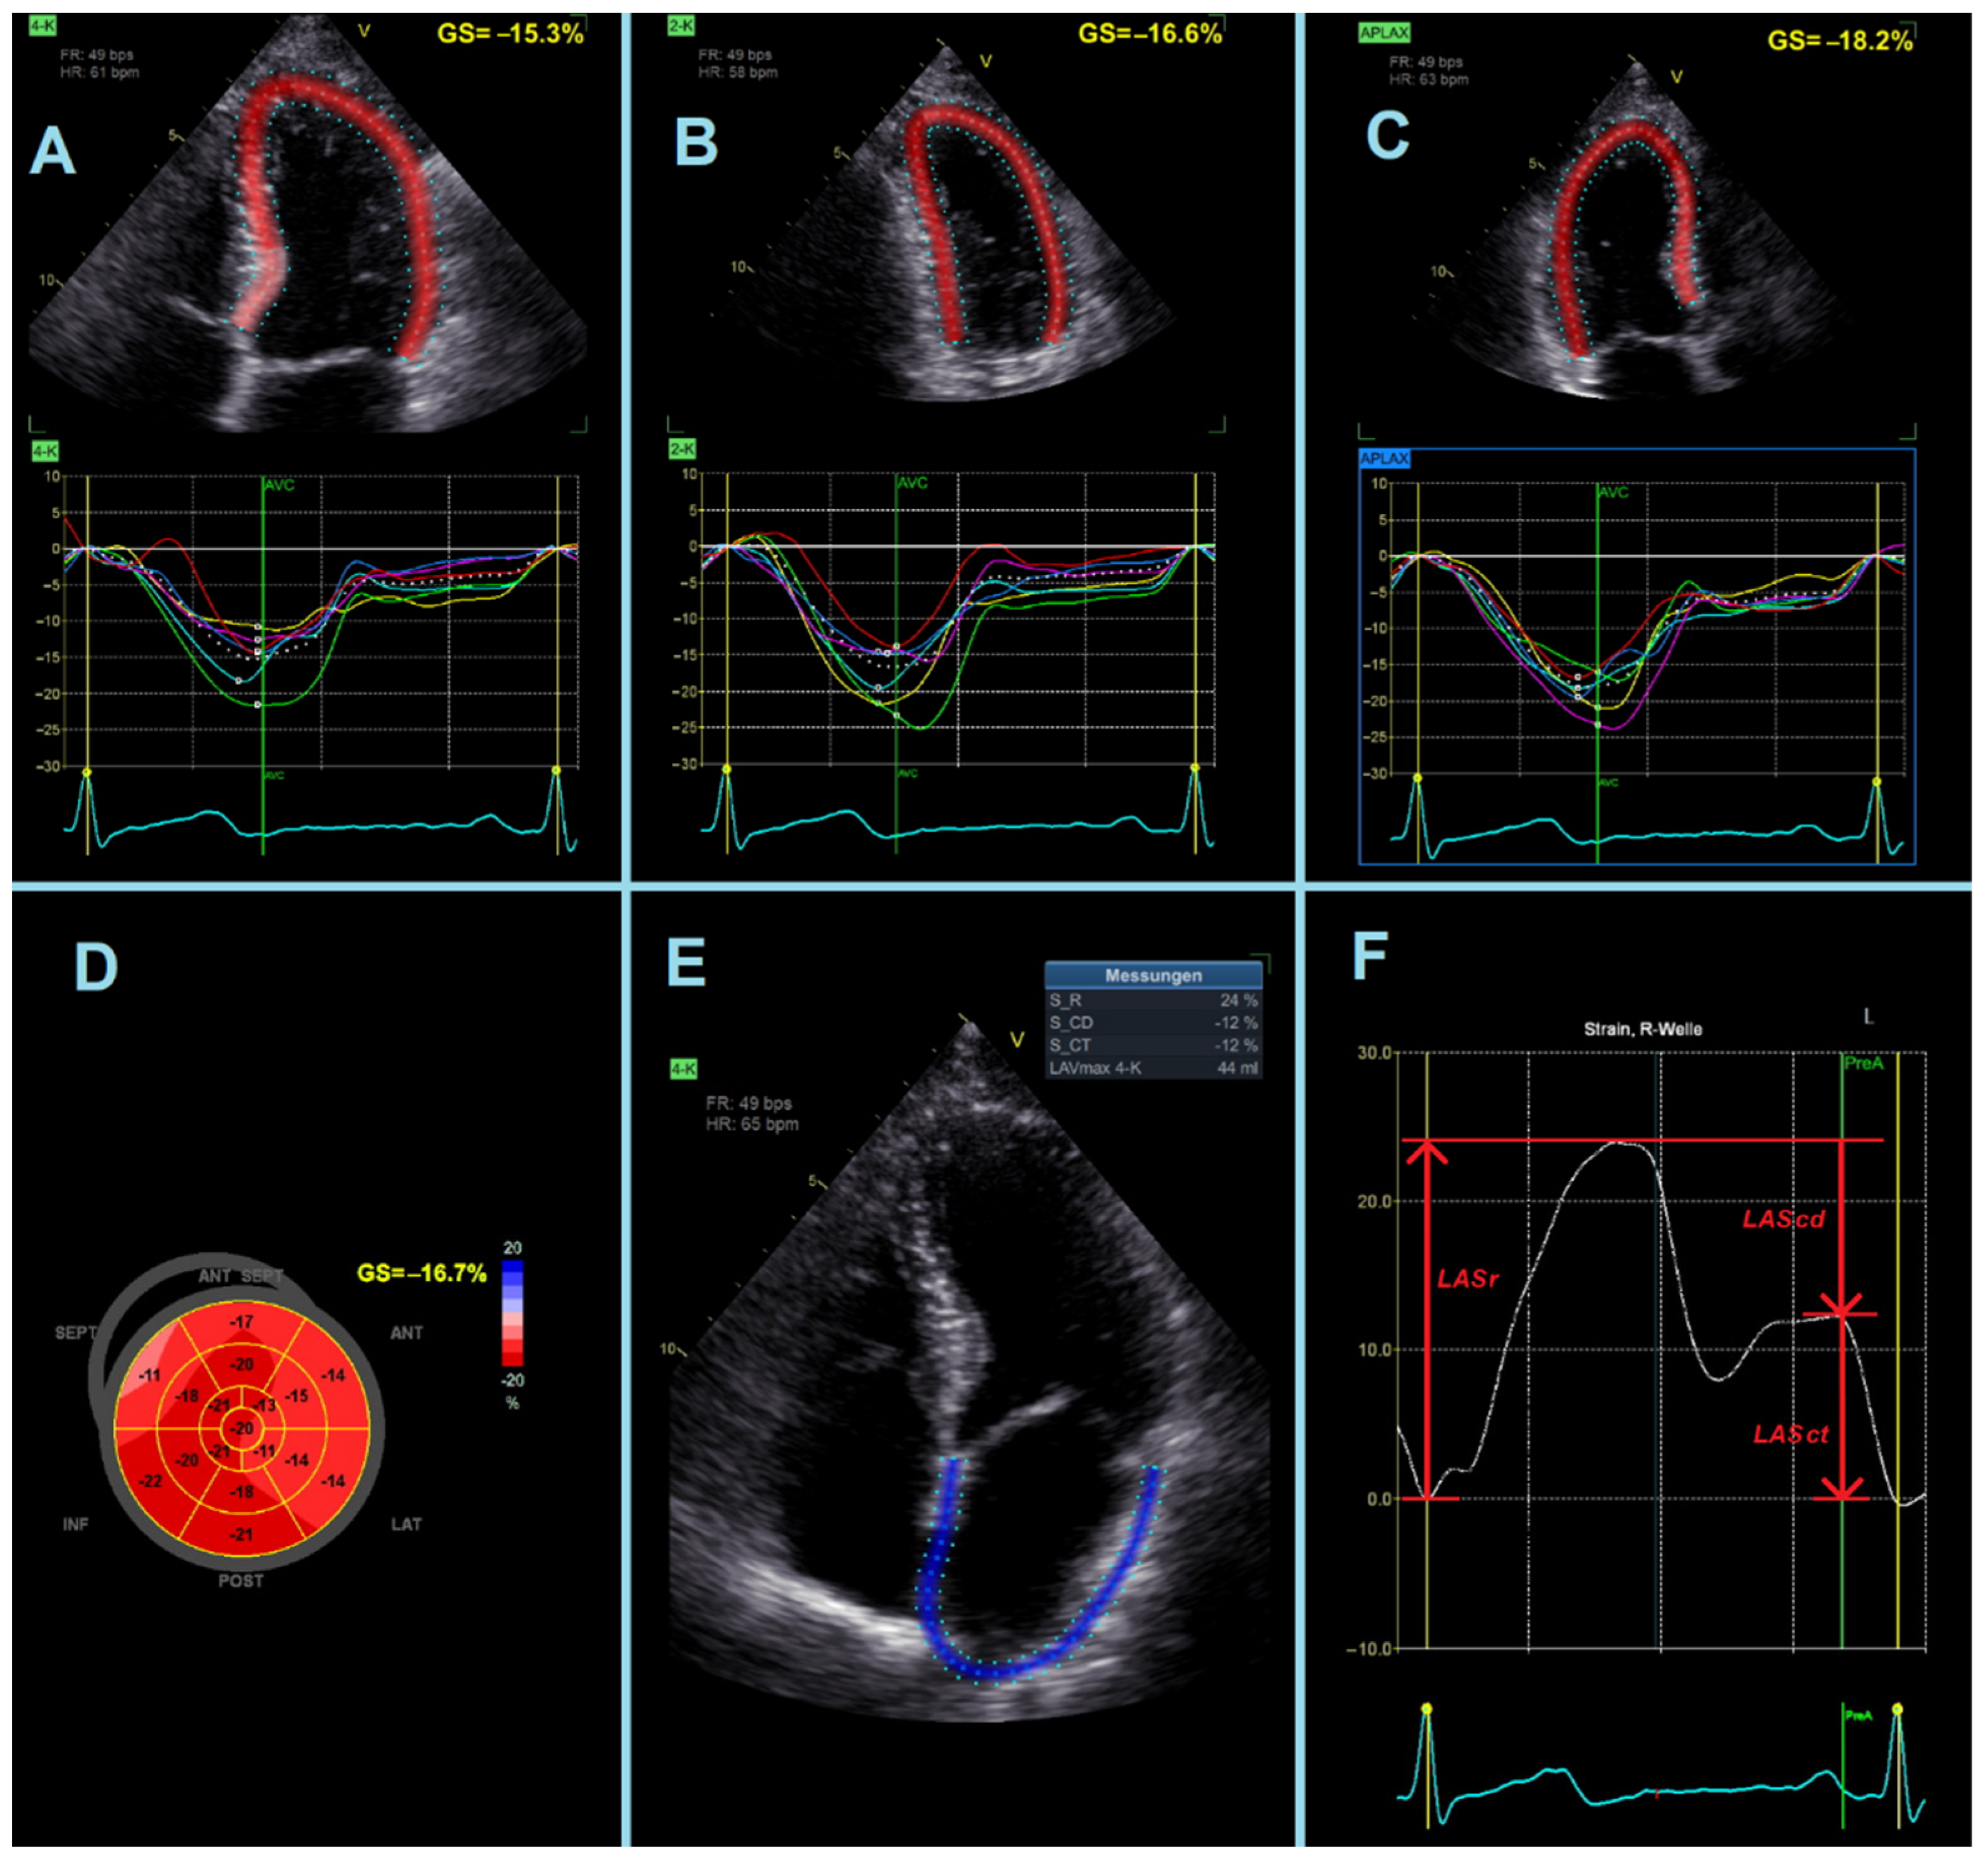

- LASr = strain during reservoir phase, measured as the strain value from the ventricular end-diastole to the mitral valve opening at ventricular end-systole (positive value).

- LAScd = strain during conduit phase, measured as the strain value from the mitral valve opening to the onset of atrial contraction (negative value). In patients with atrial fibrillation, LAScd has the same value as LASr, but with a negative sign.

- LASct = strain during contraction phase, measured only in patients in sinus rhythm as the strain value from the onset of atrial contraction to ventricular end-diastole (negative value).